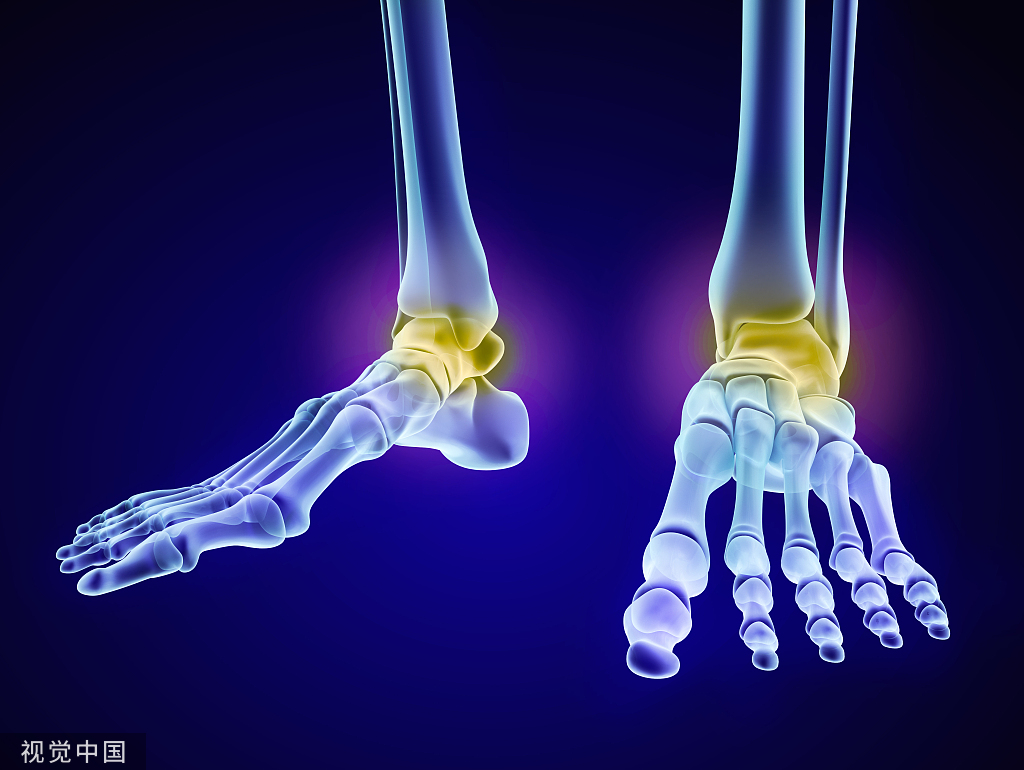

踝关节融合位置

屈曲0°、外翻5-10°、外旋5-10°、距骨轻度后移